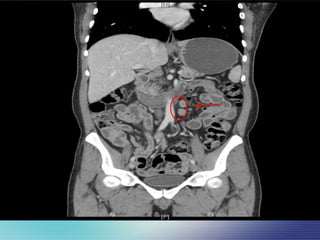

CT Abdomen

 Comparison to the previous study done

on January 2013, there is still significa

nt mesenteric lymphadenopathy.

 No hepatomegaly or splenomegaly is se

en

 Radiology Impression :

The overall picture is compatible with severe in

flammatory process of small bowel

 The differential diagnosis may include :

- Active Crohn's disease

- Infectious Enterocolitis